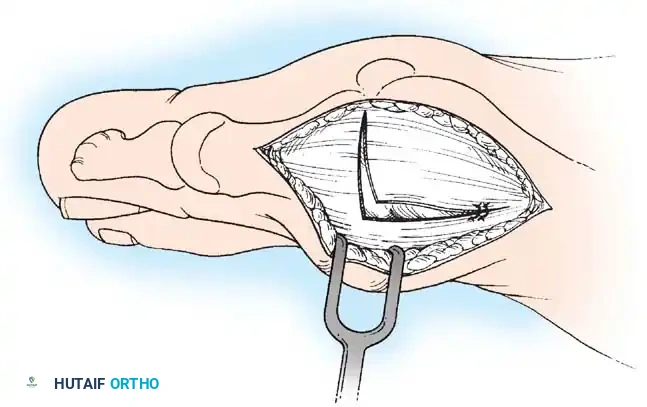

MEDIAL CAPSULAR IMBRICATION AND WOUND CLOSURE

• With an assistant holding the metatarsophalangeal joint in a congruously reduced position in the varus-valgus and fl exionextension planes, imbricate the medial capsule in the following manner (Fig. 78-22).

• Using absorbable 3-0 or interrupted sutures, place the initial suture through the plantar fl ap of the capsule at a point 4 to 5 mm medial to the proximomedial border of the medial (tibial) sesamoid and in an outside-to-inside direction.

• Turn the needle on itself, and pass it through the dorsal fl ap at the same level in an outside-to-inside direction. Immediately pass the suture back through the dorsal fl ap from inside out and fi nally through the plantar fl ap from inside out (a swedged-on needle would suffi ce, but a small, cutting needle is recommended).

• With the hallux held in the desired position, tie this suture, bringing the plantar fl ap over the dorsal fl ap and pulling the plantar-displaced abductor hallucis toward the midline of the longitudinal axis of the proximal phalanx and fi rst metatarsal.

• Allow the toe to rest unassisted to judge its resting posture and the tension on the capsular repair.

• If the fi bular sesamoid has been removed, do not imbricate the medial capsule, to avoid pulling the tibial sesamoid medial to the metatarsal head (Fig. 78-23). If a large medial eminence has persisted for many years with increased capsular reaction and redundancy, a portion of the dorsal fl ap may need to be excised before closure.

• It is imperative to avoid pulling the medial side of the tibial sesamoid medial to the articular surface of the fi rst metatarsal head; do not uncover the tibial sesamoid (Fig. 78-24).

• If the resting posture of the hallux is acceptable, close the remaining portion of the capsule with interrupted 2-0 or 3-0 absorbable sutures.

CLOSURE OF THE INVERTED-L CAPSULOTOMY

• Begin the closure proximally using 3-0 sutures on a small swedged-on needle; bending the needle to increase the curve makes passage easier in a small wound (see Fig. 78-16E).

• While an assistant applies tension distally on the free corner of the capsule, place the most proximal suture in the longitudinal limb of the capsular incision; place two or three sutures at 5-mm intervals. Do not place the corner suture.

• Begin to close the transverse limb of the incision at the medial plantar corner.

• Hold the hallux reduced on the metatarsal head while tying all sutures.

• Unless the capsule is redundant, do not imbricate the medial capsule over the area of eminence removal. Close this portion of the transverse limb with side-to-side sutures, and place the imbricating suture in the dorsomedial corner of the capsulotomy.

• Begin this fi nal suture distally on the transverse limb of the inverted L , passing the needle from the outside in.

• Reverse the needle, and enter the capsular fl ap from the outside in on the transverse limb.

• Reverse the needle, and reenter the capsular fl ap from the inside out on the longitudinal limb of the fl ap.

• Make the fi nal pass of the needle from the inside out on the dorsal side of the longitudinal limb of the incision. Holding the joint in its reduced position, tie the suture.

• If the joint reduction is congruent, but the hallux is still in an unacceptable valgus position, metatarsal osteotomy should be considered.

• If the transverse limb of the capsular repair is too loose, allowing the hallux to slide into valgus, remove the midline medial suture in the transverse limb. While holding the hallux in the proper position, place the suture 2 to 3 mm farther away from the incision, or excise more capsule from the proximal portion. Take care in removing any extra capsule because removal of even a small portion results in a signifi cant correction of capsular laxity and may cause varus of the hallux.

• At the conclusion of the procedure, the hallux should rest on the metatarsal head in about 5 degrees of valgus and 10 degrees of extension.